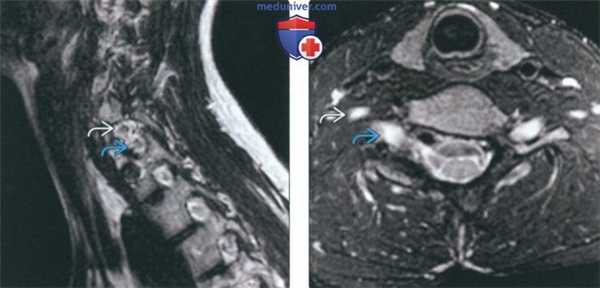

(Слева) На сагиттальной МРТ (Т2 ВИ) отсутствует правая ножка С7, сформировано патологическое широкое отверстие, содержащее корешки С7 и С8.

(Справа) На аксиальной МРТ (Т2 ВИ FS) определяется отсутствие правой ножки С7 с наличием широкого межпозвонкового отверстия, в котором находятся корешки С7 и С8.